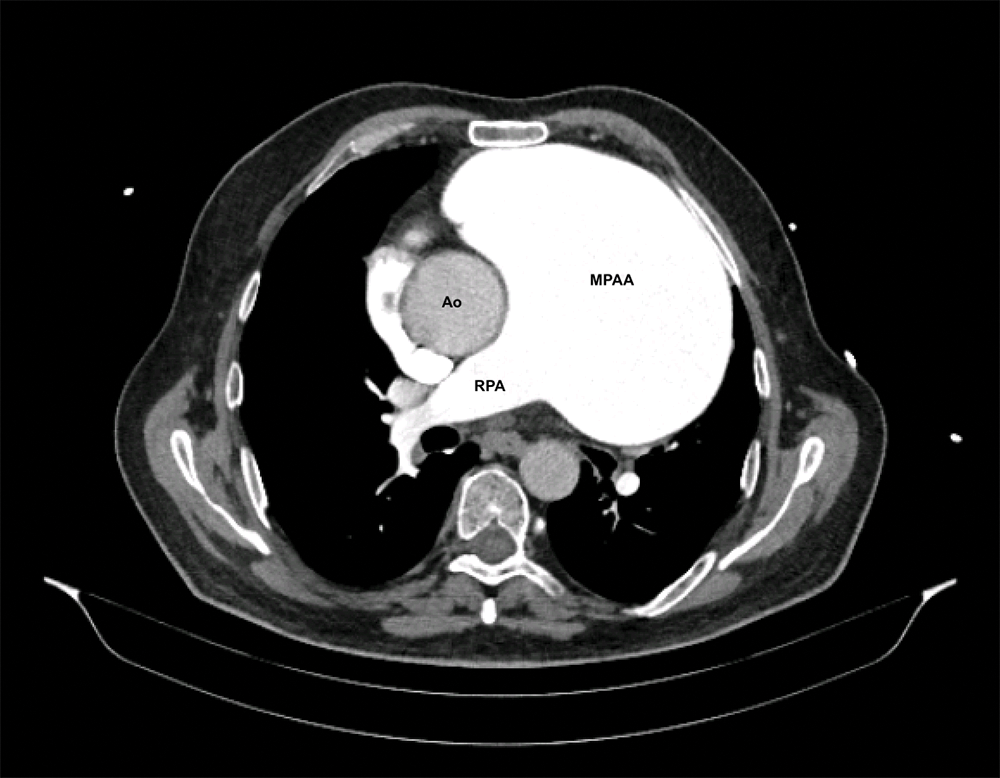

Four months before admission, he was admitted to the emergency department of our institution due to acute right heart failure exacerbation. During the in-hospital stay, echocardiography was performed and revealed situs solitus, dextrocardia, and severe tricuspid regurgitation due to a mild form of Ebstein anomaly (type A by Carpentier classification) with incomplete delamination of the septal leaflet and malcoaptation due to severe annular and right ventricle and right atrium dilatation in long-standing disease (Fig. 1). There was no displacement of the inferior leaflet hinge point and no significant rotation of the tricuspid valve, but the septal leaflet offset was apically displaced by 21 mm (indexed by body surface area (BSA) 9 mm/m2) in comparison with the mitral valve, which is slightly above the cut-off value for establishing Ebstein anomaly diagnosis (Fig. 1). Additionally, echocardiography showed an abnormal pulmonary valve with moderate pulmonary regurgitation, mild pulmonary stenosis, and severely dilated main pulmonary artery and pulmonary artery branches (Fig. 2). The patent foramen ovale with left-to-right shunting was established as well. On the ECG atrial flutter and left bundle branch block were observed. Right heart catheterization showed an absence of pulmonary hypertension (mean pulmonary artery pressure 17 mmHg, wedge pressure 22 mmHg, Rp/Rs 0.07, pulmonary vascular resistance 3 Wood units) and confirmed patent foramen ovale with left-to-right shunting. The peripheral oxygen saturation was 94% without oxygen supplementation. Chest CT scan showed a large main pulmonary artery aneurysm, 10.4 cm in diameter, with dilated left and right pulmonary arteries (2.8 and 3.2 cm in diameter, respectively) (Figs. 3 and 4).

Figure 3: CT angiography shows a giant-size main pulmonary artery aneurysm (MPAA–main pulmonary artery aneurysm, RPA–right pulmonary artery, Ao–ascending aorta)